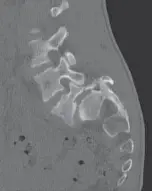

صورة توضيحية لـ الانزلاق الغضروفي القطني والانزلاق الفقاري البرزخي: دليلك الشامل للتشخيص والعلاج مع الأستاذ الدكتور محمد هطيف في صنعاء

• التصوير المقطعي المحوسب (CT Scan): قد يُستخدم في بعض الحالات لتقييم العظام بشكل أفضل، خاصة إذا كان الرنين المغناطيسي غير ممكن.

• التصوير المقطعي المحوسب (CT Scan): يوفر صوراً مفصلة ثلاثية الأبعاد للعظم، وهو الأفضل لتحديد موقع وخصائص كسر البرزخ.

• التصوير بالرنين المغناطيسي (MRI): مفيد لتقييم الأنسجة الرخوة مثل الأعصاب والأقراص، وتحديد مدى تأثير الانزلاق على الحبل الشوكي أو جذور الأعصاب.